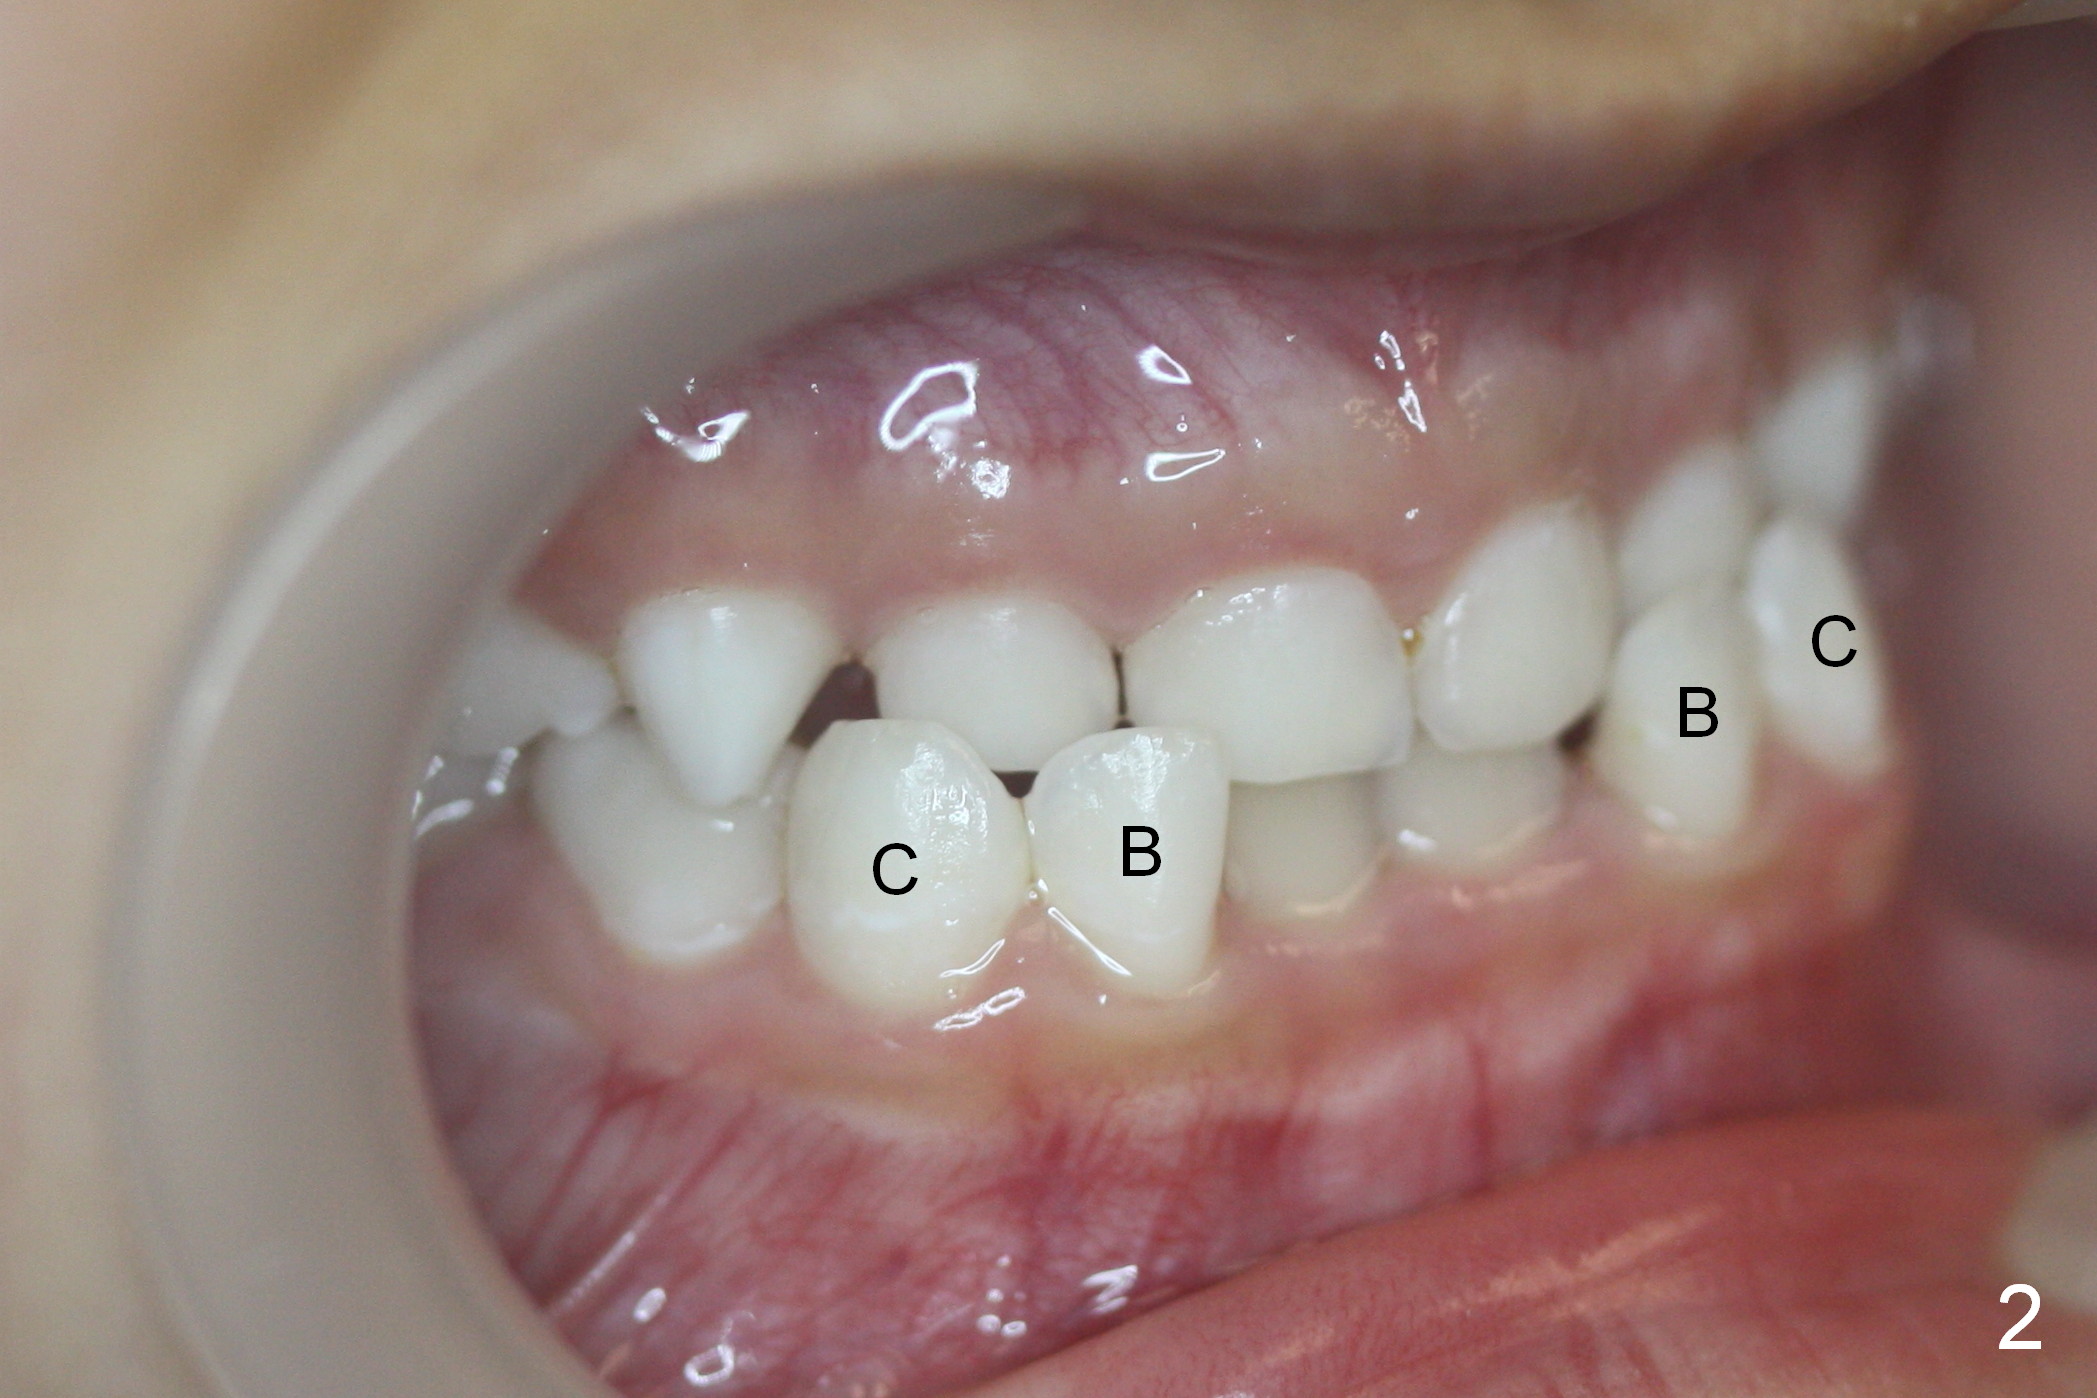

Deciduous Anterior Cross Bite

Unlike his brother, Andrew (7 years 10 months old) does not have missing teeth (Fig.1-3). But there is anterior cross bite involving the deciduous teeth (Fig.2: B, C). It appears that the permanent lower central incisors (Fig.1: #1) have erupted into the normal position (Fig.2). It is hoped that the anterior cross bite is a temporary phenomenon.